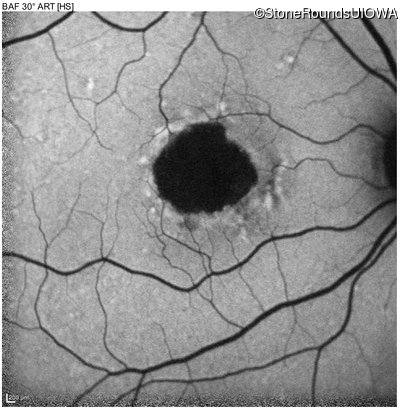

Infrared Fundus Photograph - Left - 20/160 -1 sc

Exemplar